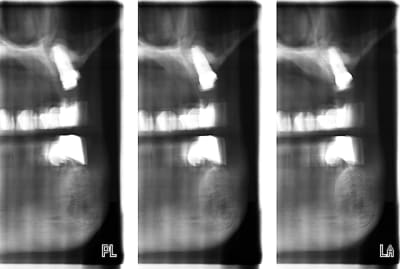

pour ceux qui en ont assez d'envoyer leur patients se faire faire un scanner et d'attendre le retour dudit patient, la solution peut s'appeller pro max;

comme son prix en version 3D m'inquiétait un peu, (+ de 100.000 €), je l'ai acheté en version allégée, sans la 3D; elle fait donc les panos et surtout les tomos (voir fichiers ci joint); les résultats sont assez intéressants; la version 3D sera ajoutée dans un an ou deux; je pense que ça ne peut pas remplacer à 100 % un scanner pour préparer un soulevé de sinus par abord latéral, mais ça le fait très bien pour le reste; pour les sinus par abord crestal, j'attend de voir

J'ai travaillé dans un cabinet d'implanto qui l'avait, le praticien en avait l'air content, mais les clichés tomos étaient très inégaux et devaient souvent être recommencés (bonjour l'irradiation), pour un résultat quand même souvent assez "impressionniste". Il est quand même assez fréquent que sur les quatre coupes, une seule "coupe" vraiment quelquechose.

Je pense que c'est plus utile pour avoir une "idée" de l'anatomie, plutôt que pour faire quelque chose de précis.

pour ma part, je n'ai pas encore raté de tomos, 4 réussies sur 4, j'en suis donc content;

pour les résultats "impressionnistes", que penses tu des fichiers en pièces jointes?

on peut faire 3 coupes espacées de plusieurs mm, la distance entre chaque coupe étant réglable; je ne connais pas encore toutes les valeurs, actuellement, je travaille sur un espace de 3 mm;